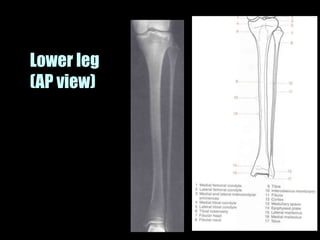

This document provides an overview of normal musculoskeletal imaging. It discusses basic x-ray concepts and densities. It then reviews normal anatomy as seen on x-rays of the skull, spine, pelvis, chest, and extremities. Key anatomical structures are labeled on example x-rays for the shoulder, hip, knee, and foot. Quizzes are included to test recognition of anatomical structures and patient age based on x-rays.